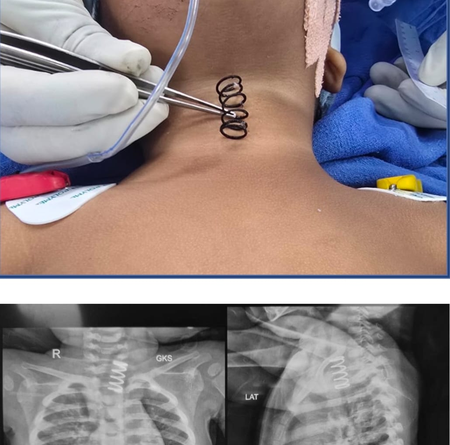

Read moreAhmedabad, Feb 24: Seven children with severe spinal deformities underwent successful surgeries at the Government Spine Institute in Ahmedabad Civil